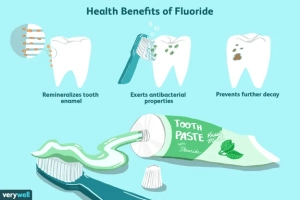

نقش واقعی فلوراید در محافظت از دندان ها

فلوراید مانند «معلم صبور» دندان ها عمل می کند — هر بار که مینای دندان در اثر اسیدهای تولید شده توسط باکتری ها دچار فرسایش می شود، فلوراید به ترمیم دوباره ساختار بلوری مینا کمک می کند. این فرآیند را Remineralization یا معدنی سازی مجدد می نامیم.

در مرحله ری مینرالیزیشن از طریق بزاق، فعالیت باکتریواستاتیک فلوراید باعث کاهش فعالیت باکتری ها جهت تبدیل کربوهیدات ها به اسید می شود. در مرحله رشد و بلوغ مینای دندان، باعث قویتر شدن مینای می شود. فلورایدی که روزانه دریافت می کنیم باعث محافظت دندان از پوسیدگی می شود. فلوراید یک ماده طبیعی است که باعث افزایش مقاومت دندان ها در برابر پوسیدگی می شود.

مصرف موضعی فلوراید (دهانشویه، خمیر دندان، ژل، وارنیش و.. ) باعث ورود آن به ساختار دندان می شود و در محکم نگهداشتن بدنه دندان مؤثر است. همچنین به میزان ۴۰ تا ۵۰% در دندان های شیری و به میزان ۵۰ تا ۶۰% باعث کاهش بروز پوسیدگی در دندان های دائمی می شود. شایان ذکر است چنانچه این امکان وجود داشته باشد، افزودن این ماده به آب آشامیدنی شهرها می تواند از جمله مؤثرترین روش های پیشگیری از پوسیدگی دندان باشد.

2. پیشگیری از پوسیدگی دندان: دفاع بی ادعای علم

پوسیدگی دندان فرایندی تدریجی است که از لحظه تماس قند با باکتری های دهان آغاز می شود. این باکتری ها اسید تولید می کنند و این اسید، کلسیم و فسفات را از مینا خارج می سازد. فلوراید در این میان مانند مهندس ترمیمی نامرئی عمل می کند:

با بازگرداندن مواد معدنی به بافت مینا، مانع پیشرفت آسیب می شود.

مشخص شده است که مکمل فلوراید از پیشرفت روند پوسیدگی دندان در نوزادان، کودکان و افراد بزرگسال جلوگیری می کند. فلوراید این اثر مفید را از طریق تماس مستقیم روی دندان ها اعمال می کند و همچنین از دندان های در حال رشدی که هنوز زیر لثه ها هستند، در برابر ایجاد حفره هایی که بالأخره روی دندان ها ایجاد خواهند شد محافظت می کند.

اعتقاد بر این است که فلوراید از دو طریق به جلوگیری از پوسیدگی دندان کمک می کند: با جلوگیری از رشد بیش از حد باکتری ها و معدنی کردن دندان ها.

پیشگیری از رشد بیش از حد باکتری ها

نشان داده شده است که فلوراید رشد بیش از حد باکتری های خاصی که ممکن است در ایجاد پوسیدگی دندان نقش داشته باشند، را کاهش می دهد. فلوراید سطح pH دهان را کاهش می دهد، و باعث می شود محیط دهان اسیدی تر شود و کمتر میزبان باکتری ها باشد.

معدنی سازی دندان ها

فلوراید در تعامل با دندان ها، ماده ای به نام فلوراپاتیت fluorapatite تشکیل می دهد که دندان ها را معدنی می کند. مینرالیزیشنMineralization یا معدنی کردن، فرآیند سخت شدن شیمیایی است، اثری که از دمینرالیزیشن (تجزیه مواد معدنی) دندان جلوگیری می کند. جالب اینجاست که، گرچه فلوراپاتیت بخش طبیعی دندان ها نیست، اما مفید است و باعث بروز هیچ آسیبی به دندان ها نمی شود.